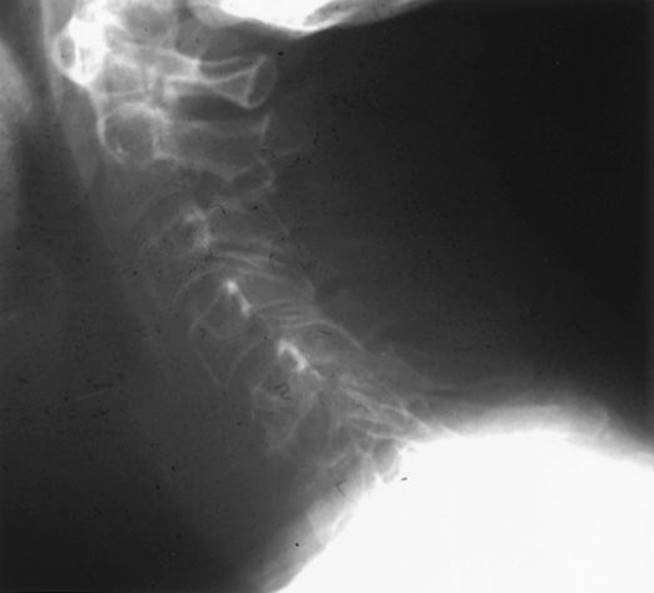

a. Plain X-rays can show destruction of the vertebral bodies and pedicles (Fig. 22.4). Pathologic compression fractures and lytic pedicles are very common. The sensitivity of plain X-rays is approximately 60%.

FIGURE 22.4 Lateral radiograph demonstrating lytic destruction of the C6 vertebral body.